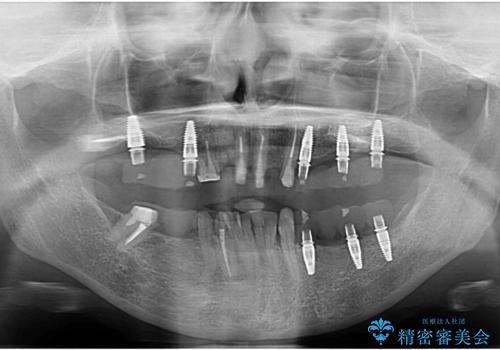

多発した虫歯による咬合崩壊 インプラントを用いた全顎治療

歯の破折・再発した大きな虫歯・根尖病変・歯の欠損、これらの問題を根管治療・歯周外科・インプラント治療・セラミック補綴を行うことで一つづつ解決し安定した咬合状となるよう治療を進めます。

全顎治療について

口腔内全体を治療する全顎治療は、期間も長く外科を行う回数も多いためしっかりと通っていただくことが必要不可欠になります。